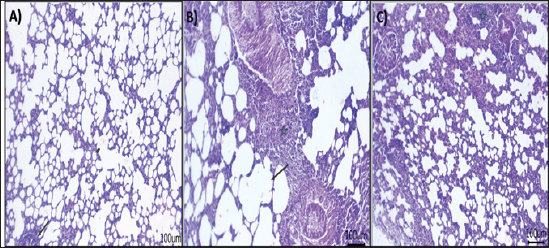

Morphological changes of the lung tissues

Next, the effect of AV-CS-NPs injection on lung histology was examined after administration of S. aureus. The lungs of the control rat group showed normal structures of bronchi, bronchioles, alveolar epithelium, and pulmonary vasculatures (Fig. 6A). On the contrary, the S. aureus-treated group exhibited pneumonic areas alternated with emphysematous areas. The pneumonic areas showed impacted alveolar lumina with different leukocytic infiltrates. Some bronchioles showed necrotic bronchiolitis which is represented by necrotic and desquamated lining epithelium leaving a denuded surface. Moreover, inflammatory cells aggregate within the bronchiolar wall and were also seen primarily as eosinophils and neutrophils (Fig. 6B). These pathological findings were improved after AV-CS-NPs treatment. Most of the pulmonary tissue showed maintained structures upon pretreatment with AV-CS-NPs (Fig. 5C). However, perivascular inflammatory cells aggregate (star) and dilated perialveolar capillaries were also seen in some examined fields (Fig. 6C).

Fig. 6. Photomicrograph of H&E stained section from experimental groups: (A) control group: lung tissue showing normal structures of bronchiole and alveoli, (B) S. aureus group: lung tissue showing necrotic and desquamated lining epithelium of bronchiole leaving the denuded surface with inflammatory cells aggregates within bronchiolar wall mainly eosinophils, (C) AV-CS-NPs + S. aureus group: lung tissue revealed maintain structures, but perivascular inflammatory cells aggregates (star) and dilated perialveolar capillaries were also seen in some examined fields. Scale bar 100 μm.